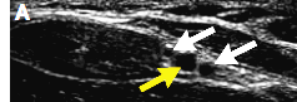

图4.横断面定位下置管

超声探头横断面定位下(A)细针插入桡动脉(B,箭头)